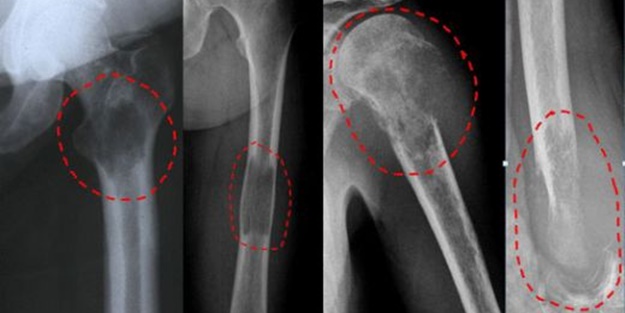

Basit kemik kisti

Nedir?: Kemiklerin içinde, İçi sıvı dolu, yavaş seyirli, genişleme özelliği gösteren kistlerdir. Daha çok çocukluk ve ergenlik döneminde görülür. Erkek çocuklarda sıktır. Kistler vücutta en çok kol kemiği ve uyluk kemiği üst bölgesinde bulunur. Çoğunlukla kemiğin metafiz (Uç) bölgesinde yerleşir. Bu kistleri büyüme durumlarına göre aktif kist ve latent kist olarak sınıflandırabiliriz. Aktif kistler büyüme plağına yaslanmış durumdadır ve yavaş bir seyirle genişleyerek tüm metafizi doldurabilir. Bu nedenle de patolojik kırık riski taşırlar. Büyüme plağından uzaklaştıkça kistlerde büyüme yavaşlar bu kistlere ise latent kist demekteyiz.

Klinik: Birçok basit kemik kistinde klinik bulgu yoktur. Tesadüfen başka bir nedenle çektirilen radyografilerde tespit edilir. Büyük kistlerde kemiğe yük bindiği durumlarda ağrı ve patolojik kırıkla bize başvurabilirler.